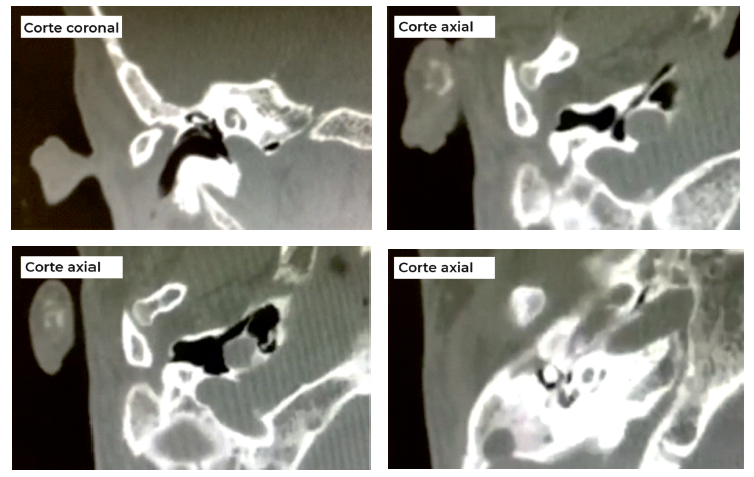

A TC de ouvidos (fig. 3 ) revelou à direita atrésia membranosa do CAE, displasia do ouvido médio com cabo do martelo rudimentar, indefinição da articulação incudomaleaolar e incudoestapédica. O canal carotídeo apresentava uma protusão e encontrava-se deiscente a nível do ouvido médio. O ouvido esquerdo não apresentava alterações.

O sistema de classificação de Jahrsdoerfer4 atribui uma pontuação anatómica (1-10) ao ouvido atrésico com base na presença/ausência de 9 estruturas, com o estribo a representar 2 pontos (tabela 3). A escala não só avalia a indicação cirúrgica do doente, como ajudar a prever o resultado audiométrico, de tal forma que quanto maior a pontuação, maior a probabilidade de recuperação auditiva pós-operatória4,9. A má pneumatização do ouvido médio e mastoide foi o melhor preditor de maus resultados pós-operatórios4. Doentes com uma pontuação superior a 6 são geralmente bons candidatos à cirurgia. No nosso caso a doente apresentava uma pontuação de 6 (tabela 3), não sendo então uma boa candidata à canalplastia (cadeia ossicular não favorável, dúvida na integridade da articulação incudoestapédica, mastoide pouco pneumatizada e microtia grau II).